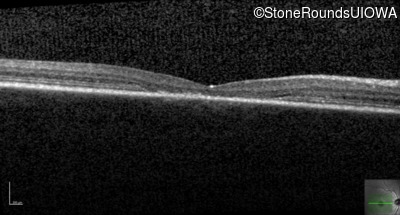

Optical Coherence Tomography - Right - 20/80 -1

Exemplar / OCT Stack

OCT Stack